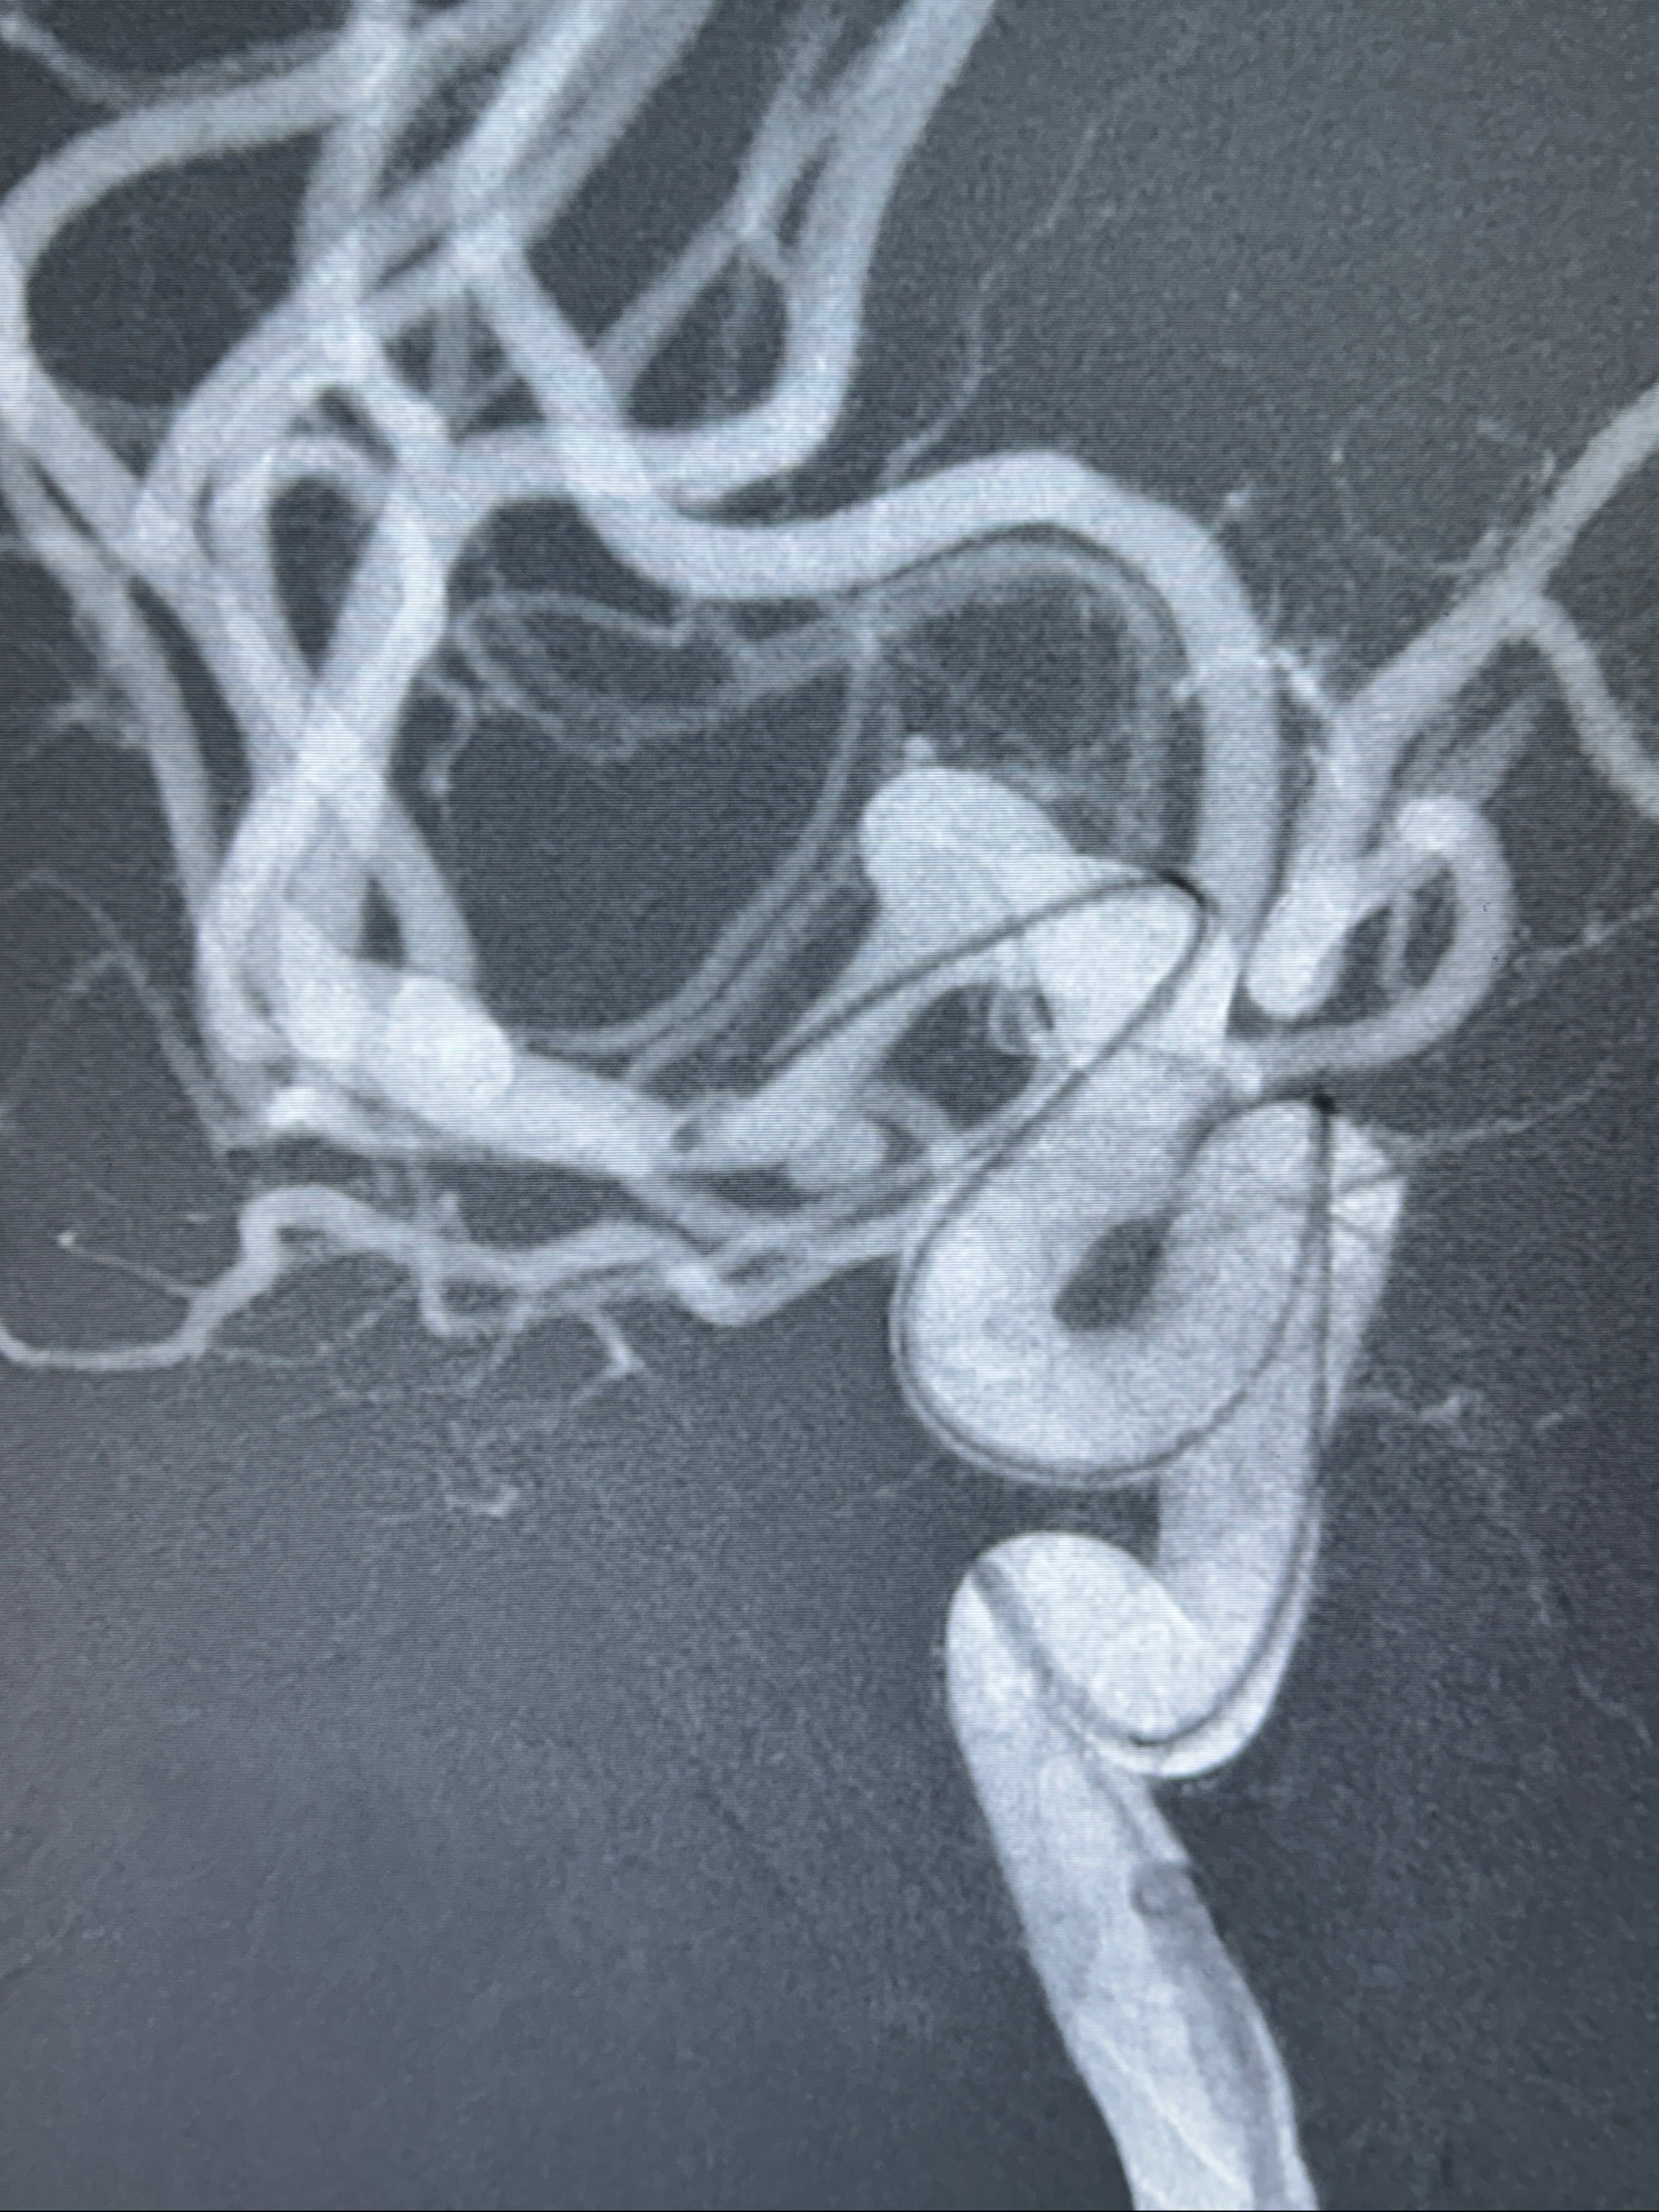

2023-12-04全麻下行支架辅助治疗

S-AB4-20mm

麻醉苏醒佳,遵嘱动作